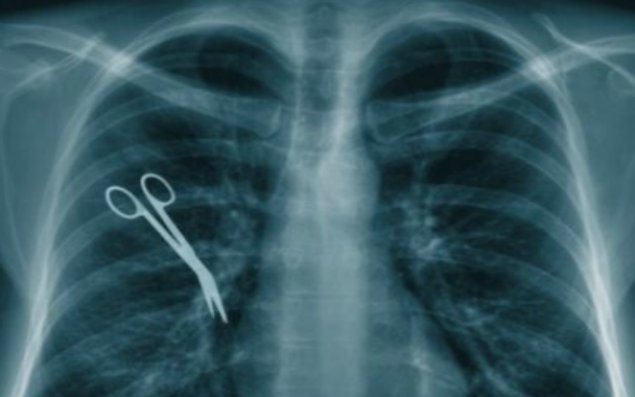

Türkiyənin Əskişəhər şəhərində həkimlərin səhlənkarlığı ölkədə geniş rezonas yaradıb. 2010-cu ildə bir qadını əməliyyat edən cərrahların, xəstənin qarnında unutduğu əməliyyat aləti 5 il sonra rentgen müayinəsi ilə üzə çıxıb.

Aktual.az Atv-yə istinadən xəbər verir ki, 4 övlad anası olan Xanım Özgül xərçəng xəstəliyi ilə mübarizə apardığından, cərrahlar təhlükəli hüceyrələrin bədəndən kəsilərək çıxarılmasına qərar verib. Qadının bətnində aparılan əməliyyat uğurlu keçsə də, onun fəsadları 5 il sonra məlum olub. Sən demə həkimlər, damar tutmaq üçün istifadə olunan aləti, əməliyyatın sonunda qadının qarnından çıxarmağı unudub. Əməliyyatdan sonra yaralaları sağalan 67 yaşlı qadın evə buraxılıb və o 5 il qarnındakı metal alətlə yaşayıb.

Qarın nahisəsində yenidən ağrılar hiss edən qadın rentgen müayinəsindən keçəndə, nə o gözlərinə inana bilib, nə də həkimlər. Onun qarın boşluğunda tibbi alətin olduğunu görən cərrahlar Xanım Özgülü yenidən əməliyyat edərək metal əşyanı çıxarıblar.

Cərrahlar səhvlərini 5 il sonra düzəltsələr də, zərərçəkənin ailəsi xəstəxananı məhkəməyə verib. Həkimlərin günahı sübuta yetirilsə, onda xəstəxana rəhbərliyi Özgül ailəsinə təzminat ödəmək məcburiyyətində qalacaq.